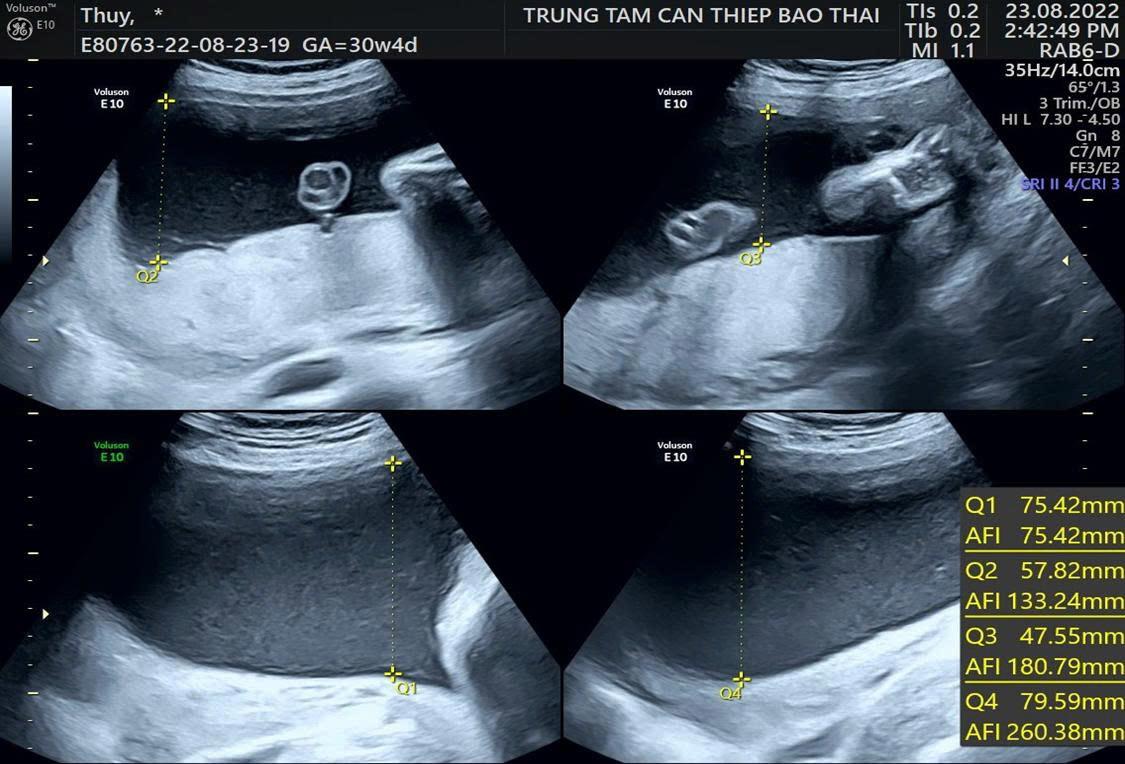

Đa ối được xác định khi chỉ số ối AFI ≥ 25 cm hoặc góc ối sâu nhất MVP ≥ 8 cm trên siêu âm. Đa ối được phân loại theo mức độ dựa trên chỉ số nước ối AFI: nhẹ (25–30 cm), trung bình (30,1–35 cm) và nặng (>35 cm).

Trường hợp đa ối nhẹ, bác sĩ sẽ xác định khi độ sâu túi ối dao động 8–11 cm, chiếm tới 80% tổng số ca ghi nhận. Phần lớn thai phụ không cần can thiệp điều trị nhưng nguyên nhân hay gặp là đái tháo đường thai kỳ cần điều chỉnh chế độ ăn uống, hạn chế tinh bột, thức ăn nhiều đường và siêu âm định kỳ để đánh giá lượng ối.

Trường hợp đa ối trung bình chiếm khoảng 15% trường hợp cần theo dõi thường xuyên hơn. Nếu thai phụ xuất hiện biểu hiện bất thường như khó thở, đau bụng, cảm giác bó chặt vùng ngực hoặc dấu hiệu nghi ngờ suy thai, bác sĩ sẽ yêu cầu nhập viện theo dõi liên tục nhằm tránh sinh non hoặc vỡ ối sớm.

Trường hợp đa ối nặng, túi ối sâu vượt trên 16 cm, cần thực hiện thủ thuật chọc ối để hút bớt ối, giảm áp lực trong buồng tử cung, giảm triệu chứng căng tức bụng, khó thở và ngăn ngừa nguy cơ sinh non. Mẫu dịch ối sẽ được gửi đến phòng xét nghiệm để phân tích nhiễm sắc thể, tầm soát nhiễm trùng nhóm TORCH và đánh giá các rối loạn tế bào học nếu có chỉ định, từ đó xác định chính xác nguyên nhân và đưa ra chiến lược điều trị phù hợp.